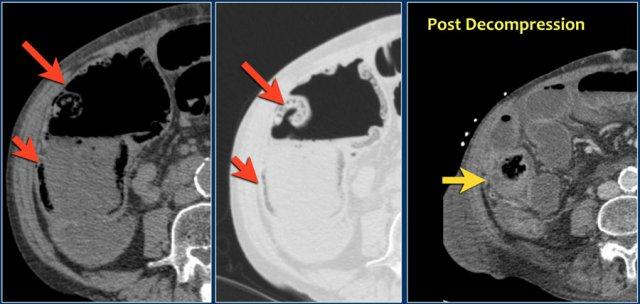

Đây là một bệnh nhân khác bị thiếu máu cục bộ một đoạn dài ruột non do tắc ruột quai kín.

Một đặc điểm hình ảnh quan trọng của tắc ruột quai kín là hình ảnh các quai ruột non giãn xếp theo kiểu nan hoa bánh xe với các mạch máu mạc treo hội tụ về một điểm trung tâm.

Các dấu hiệu thiếu máu cục bộ trong tắc ruột quai kín tương tự như ở các bệnh nhân có nguyên nhân thiếu máu cục bộ mạc treo khác:

- Dày thành ruột

- Phù nề mạc treo ruột

- Cổ trướng

- Sự ngấm thuốc của thành ruột trong thiếu máu cục bộ có thể bình thường, tăng do hiện tượng tái tưới máu, hoặc giảm/mất ngấm thuốc như trong trường hợp này.

Đây là một trường hợp tắc ruột quai kín khác.

Lưu ý sự khác biệt về mức độ ngấm thuốc giữa các quai ruột bình thường không giãn (mũi tên xanh lá) và các quai ruột giãn bị thắt nghẹt (mũi tên đỏ).

Ở trung tâm là các mạch máu mạc treo bị xoắn vặn (mũi tên vàng).